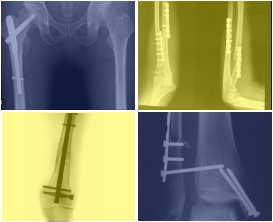

Por primera vez el Centro Médico Teknon – Grupo Quirónsalud acoge el I Curso de Osteosíntesis "Actualización del tratamiento quirúrgico de las fracturas" el viernes, 1 de abril, con la participación de destacados especialistas en traumatología de los hospitales del Grupo Quirónsalud en Catalunya para intercambiar experiencias y departir sobre los últimos avances en Cirugía Ortopédica y Traumatología. En este curso de osteosíntesis o tratamiento quirúrgico de las fracturas óseas se abordarán tanto las técnicas de implantología traumatológica como de Traumatología Mínimamente Invasiva, consistentes en la práctica de nuevas vías de acceso que disminuyen el riesgo de complicaciones postquirúrgicas y acortan el tiempo de recuperación tras la cirugía.

Asimismo, se expondrán las últimas técnicas para tratar la "pseudoartrosis", una complicación que se presenta cuando las fracturas no consolidan o no se resuelven, a pesar de haberse aplicado un tratamiento quirúrgico. Entre ellas figuran dos procedimientos enormemente vanguardistas como la utilización de las células madre o el trasplante de hueso vascularizado, con los que se está empezando a obtener buenos resultados y que se presentarán en este curso.

"La osteosíntesis de las fracturas óseas es un área muy específica de la especialidad de la Cirugía Ortopédica y Traumatología, en constante evolución debido al continuo desarrollo de nuevos materiales y vías de abordaje para colocarlos. Antiguamente, el objetivo del tratamiento de las fracturas era la cicatrización o consolidación ósea, pero hoy en día este objetivo es insuficiente. La dinámica de la sociedad actual exige que la consolidación del hueso se realice en el menor tiempo posible y en ausencia de complicaciones", explica el Dr. David Roca, cirujano ortopédico y traumatólogo del Centro Médico Teknon y director del curso.